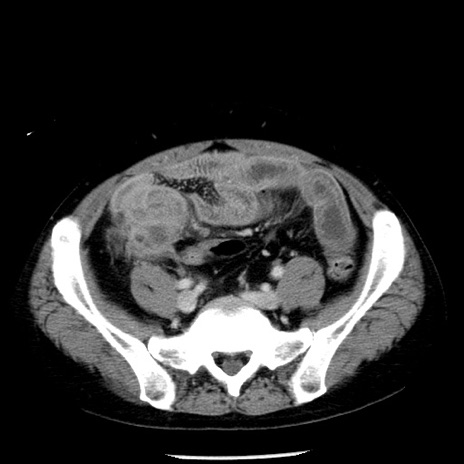

症例29(横断像)

【症例】40歳代男性

【現病歴】2日前から胃痛あり。徐々に周期的な激痛に変化した。本日になっても激痛があるため受診。

【身体所見】意識清明、BT 38-39℃台あり、腹部:膨満、やや硬、右下腹部に圧痛あり。

【データ】WBC 8500、CRP 23.26